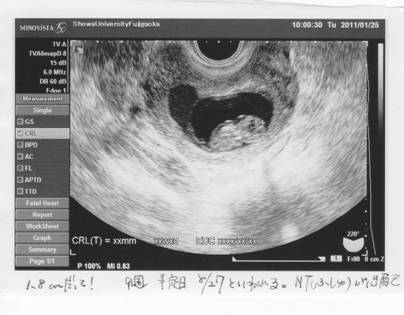

クリニックからの紹介状を携え、昭和藤が丘病院に。

出血層が、近い。

エコーは角度によって見え方が異なる?

出血があるということで、安静入院を勧められた。

出血は治まりつつあるので、外来様子見でよいか・・・となったそう。

エコーの検査で、胎児の大きさが少し小さいように思えたが、

成長は正常である。

機械も違うし角度によっても違うのだろう、と納得。

ただ・・・。

首に浮腫(NT)が見える。

これが大きくなってゆくと、ダウン症などの染色体異常や心疾患の可能性が高くなる。

1週間ではどれほど変化があるか・・・次回は11Wとなる2週間後に検査して、

大きくなっていたら羊水検査をしよう。

イキナリの急展開だ。

染色体に異常がなくとも、

浮腫が大きくなってゆくようであれば心臓に負担がかかっているということであり、

何れダメになる可能性が高くなる。

との事であった。

後頚部浮腫像(NT)は、妊娠10〜13週に現れ、14〜15週になると消失する。

その10〜13週に観察された際の浮腫の厚さが厚いほど、染色体異常や心臓疾患の危険率が上がると言われている。

とはいえ、正常である可能性の方が絶対的に高いんだけど・・・。